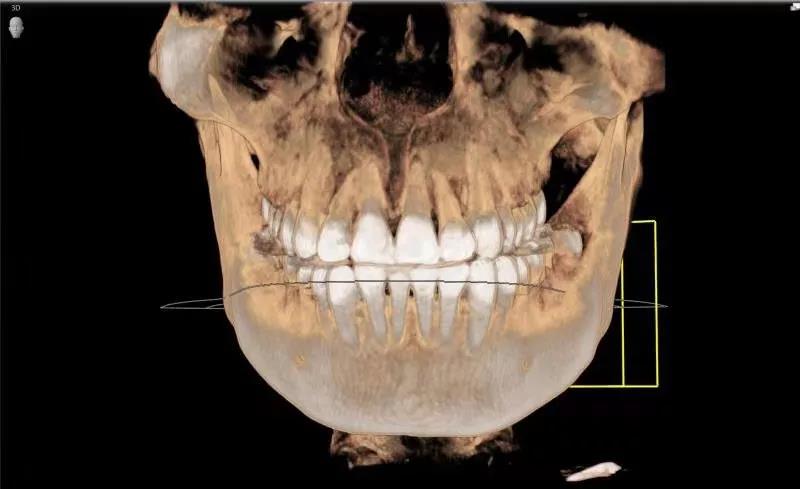

事实上,牙片是牙医的第三双眼睛。一直以为自己就长了三颗智齿呢,直到左侧6号牙坏了,拍了个牙片才知道,原来第四颗智齿长不出来了,但它一直都在。

近中阻生智齿,也就是图中1、2两颗横着向牙列方向长的智齿,非常容易将邻近的牙“顶坏”,所以不得不将这两颗牙拔掉。像智齿这样的下颌槽牙的牙根离面部神经非常近,一不小心就可能伤到神经,导致面部没有知觉。而牙片可以清晰地看到牙根与神经的距离,确定拔牙是不是有风险,这也是为什么拔牙都要拍牙片的原因。这口牙只能用“出车祸”来形容了。本以为下颌大牙先天性缺失,不曾想是牙胚的生长方向错了,大牙长不出来。

以上仅仅是列举了茫茫牙片中几个微不足道的例子,但足以说明牙片的重要性。隐藏在牙龈下方的疾病,医生光凭肉眼是无法看到的,不对症,如何用药?即使是拔除一颗坏牙,也要确定会不会伤害到下颌面部神经。由此可见,牙片是牙医的“第三只眼睛”,能看见肉眼看不到的病灶。